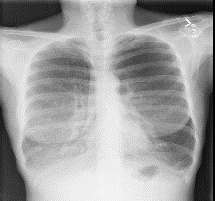

Among various medical imaging tools, chest radiographs are the most important and widely used diagnostic tool for detection of thoracic pathologies. Research is being carried out in order to propose robust automatic diagnostic tool for detection of pathologies from chest radiographs. Artificial Intelligence techniques especially deep learning methodologies have found to be giving promising results in automating the field of medicine. Lot of research has been done for automatic and fast detection of pneumothorax from chest radiographs while proposing several frameworks based on artificial intelligence and machine learning techniques. This study summarizes the existing literature for the automatic detection of pneumothorax from chest x-rays along with describing the available chest radiographs datasets. The comparative analysis of the literature is also provided in terms of goodness. Limitations of the existing literature along with the research gaps is also given for further investigation. The paper provides a brief overview of the present work for pneumothorax detection for helping the researchers in selection of optimal approach for future research.